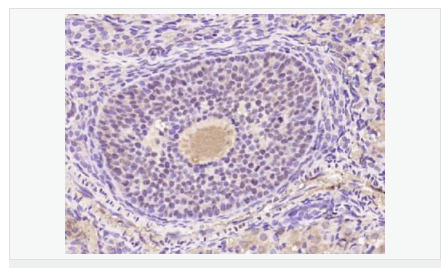

產(chǎn)品應(yīng)用WB=1:500-2000 ELISA=1:5000-10000 IHC-P=1:100-500 IHC-F=1:100-500 Flow-Cyt=1μg /test IF=1:100-500 (石蠟切片需做抗原修復)